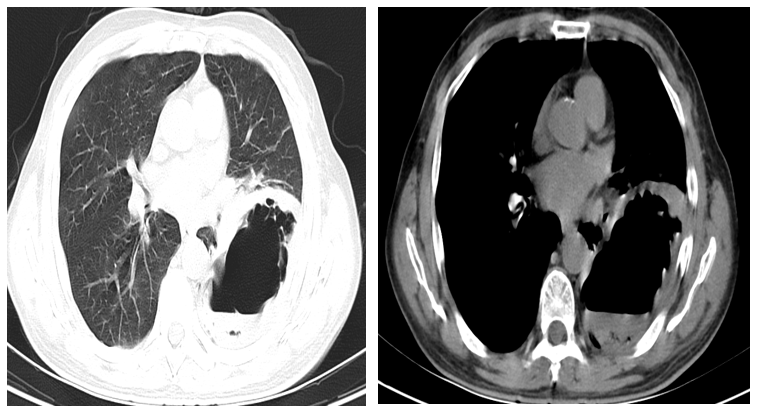

急性肺膿腫早期手術(shù)

治療前患者持續(xù)發(fā)熱4天入院。入院CT提示右側(cè)肺膿腫并胸腔積液。內(nèi)科藥物治療一周仍持續(xù)發(fā)熱。治療中肺膿腫內(nèi)科保守治療效果不佳??紤]需外科手術(shù)干預(yù)。手術(shù)方案1切除肺膿腫組織同時胸腔沖洗引流。然而手術(shù)需切除部分肺葉、損失肺功能,且急性期切除肺組織術(shù)后并發(fā)癥發(fā)生率較高。手術(shù)方案2胸腔鏡進入胸腔沖洗引流,同時肺膿腫出開窗引流肺組織內(nèi)膿液。盡可能保住肺組織。同時全程覆蓋有效抗生素。治療后治療后1年術(shù)后1年患者無任何不適癥狀。復(fù)查CT右肺僅殘留無菌空洞。治療后1月術(shù)后繼續(xù)引流及抗感染治療3天后即未再發(fā)熱。復(fù)查胸部CT肺復(fù)張良好。繼續(xù)治療1周后順利拔管出院。術(shù)后1月復(fù)查CT肺膿腫吸收、胸腔積液吸收。肺復(fù)張良好。患者無自覺癥狀。保住了患者的肺組織。